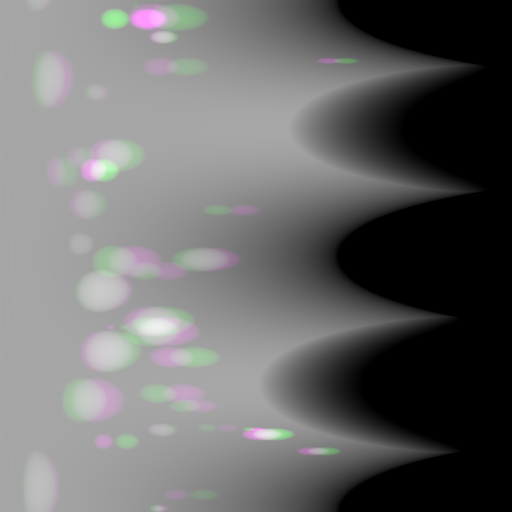

6 Limitations

Refer to caption

(a) Reference

(b) Pix2pixGAN

(c) (b)-(a)

Figure 16: An exemplary phantom contains tiny beads, where false positive and false negative tiny beads are observed. (a) is the reference image, where five zoomed-in ROIs (No. 1-5) are displayed. (b) is the Pix2pixGAN prediction image (in Cartesian form) using two complementary views in polar coordinates, where the tiny beads in ROIs No. 1-4 are hardly visible (completely missing in ROIs No. 1 and 2, while blurred in the wrong locations in ROIs No. 3 and No. 4). The tiny bead in ROI 5 of (b) does not exist in the reference image (a). (c) is the difference image.

In the experiments on numerical bead phantom data, false positive and false negative beads are observed, especially for tiny beads. The results of an exemplary phantom containing tiny beads are displayed in Fig. 16. Fig. 16(a) is the reference image where five zoomed-in regions-of-interest (ROIs) (No. 1-5) are displayed. Fig. 16(b) is the prediction image (in Cartesian form) using two complementary views in polar coordinates. The tiny beads in ROIs No. 1-4 are hardly visible. The tiny beads in ROIs No. 1 and 2 are completely missing, which are false negative cases. The tiny beads in ROIs No. 3 and No. 4 are blurred with very low contrast, and they are in wrong locations. The tiny bead in ROI 5 of Fig. 16(b) does not exist in the reference image, which is a false positive case. After checking the corresponding polar image, we observe that the tiny beads are visible in the polar image despite of low contrast. Hence, the neural network is the main reason for the missing of tiny beads instead of resampling.

Reference

0superscript00^{\circ} perspective

(a) 18.16 0.6412

Pix2pixGAN

(b) 3.53 0.9595

Figure 17: An example of perspective deformation learning from the chest data. The ROIs in (a)-(c) are displayed in (d)-(f) respectively. The tiny metal implants in (d) and (e) are missing in (f).

For experiments on simulated anatomical data, similar to the results in the numerical bead phantom experiments (Fig. 16), tiny structures, which are around 1 mm in radius, cannot be reconstructed reliably, especially when such structures are not present in the training data. For example, the tiny metal implants in Fig. 17 and Fig. 17, probably vessel stents, are hardly visible in Fig. 17.